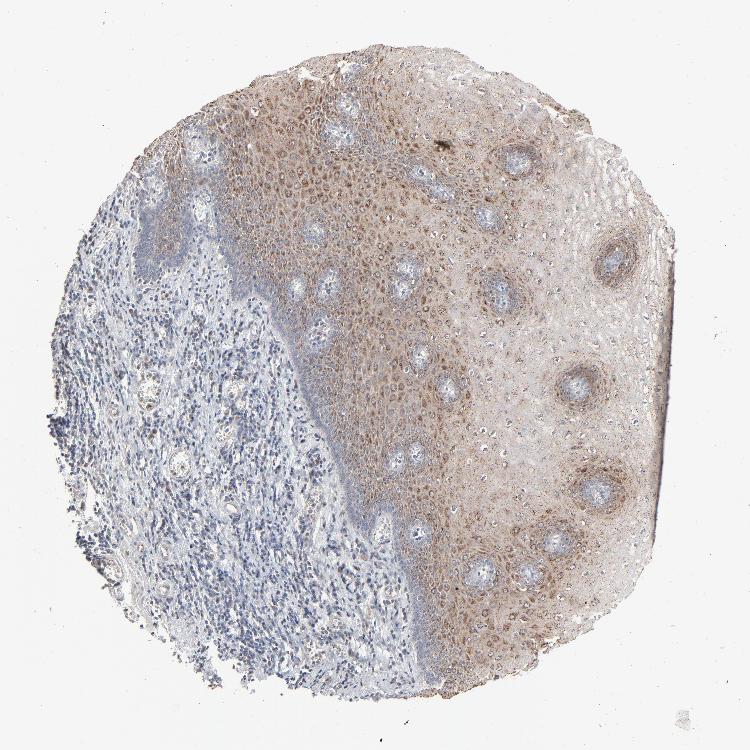

ESOPHAGUS - Antibody stainingi

Antibody staining in the annotated cell types in the current human tissue is reported as not detected, low, medium, or high, based on conventional immunohistochemistry profiling in selected tissues. This score is based on the combination of the staining intensity and fraction of stained cells.

Each image is clickable and will lead to virtual microscopy that enables deeper exploration of all samples and also displays staining intensity scores, fraction scores and subcellular localization as well as patient and tissue information for each sample.

Antibody HPA003417

Squamous epithelial cells Medium